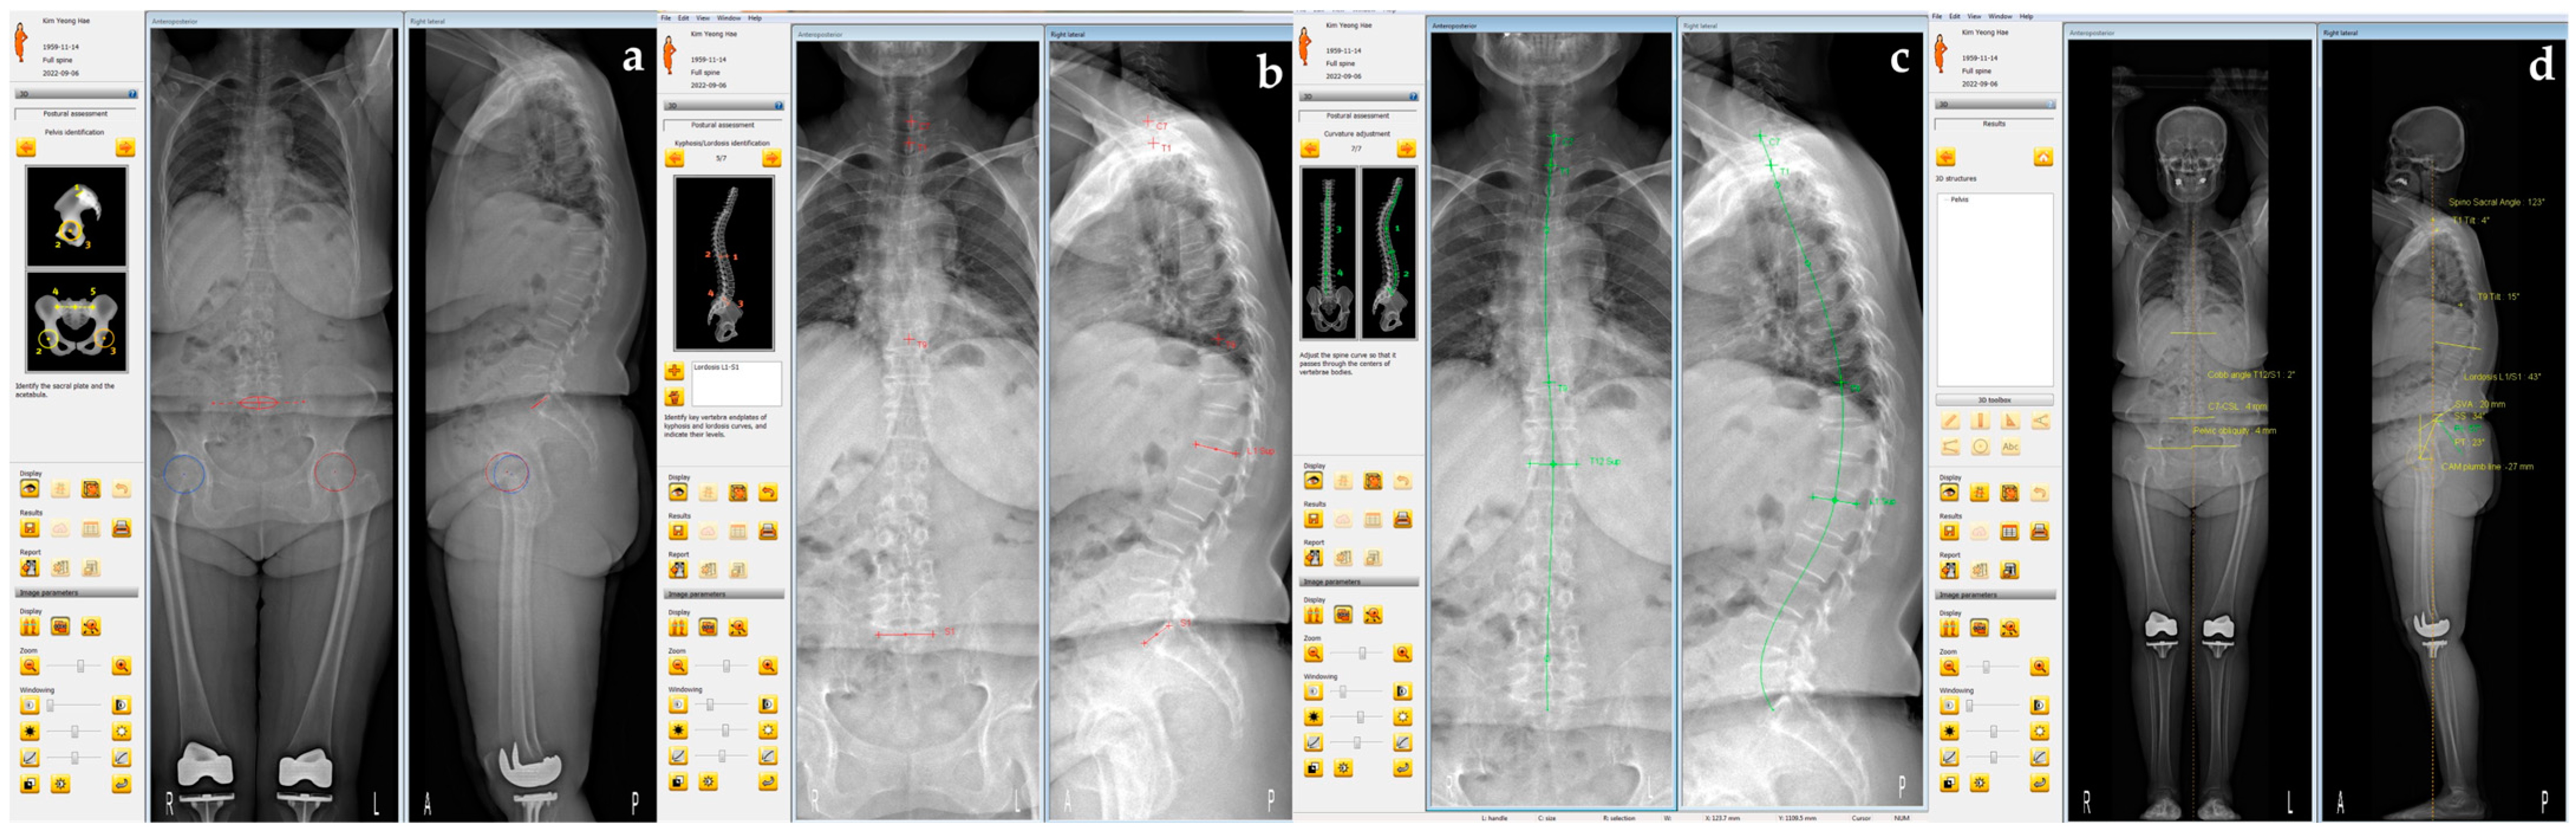

3.6. Representative Case